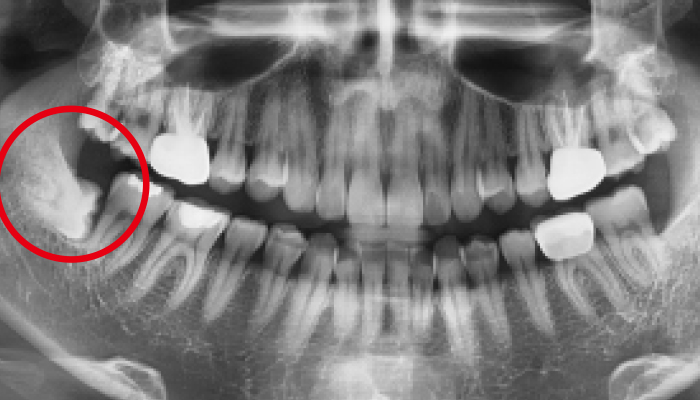

• 02 선천적 원인

안면이 비대칭이거나 올바른 턱관절 형성이 되지 않은 경우 턱관절 질환이 잘 발생합니다.